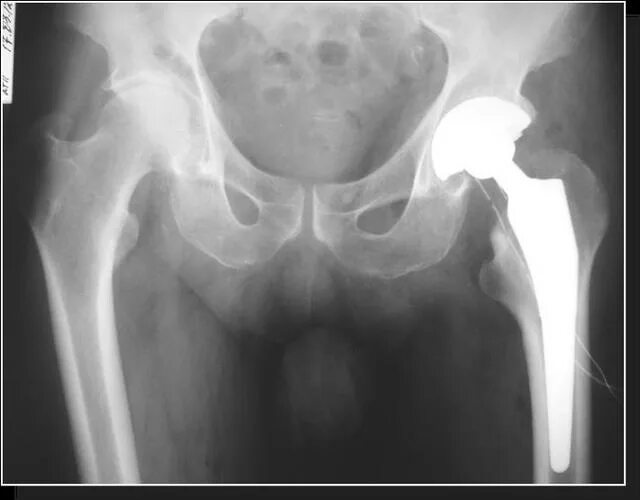

Коксартроз инвалидность какая